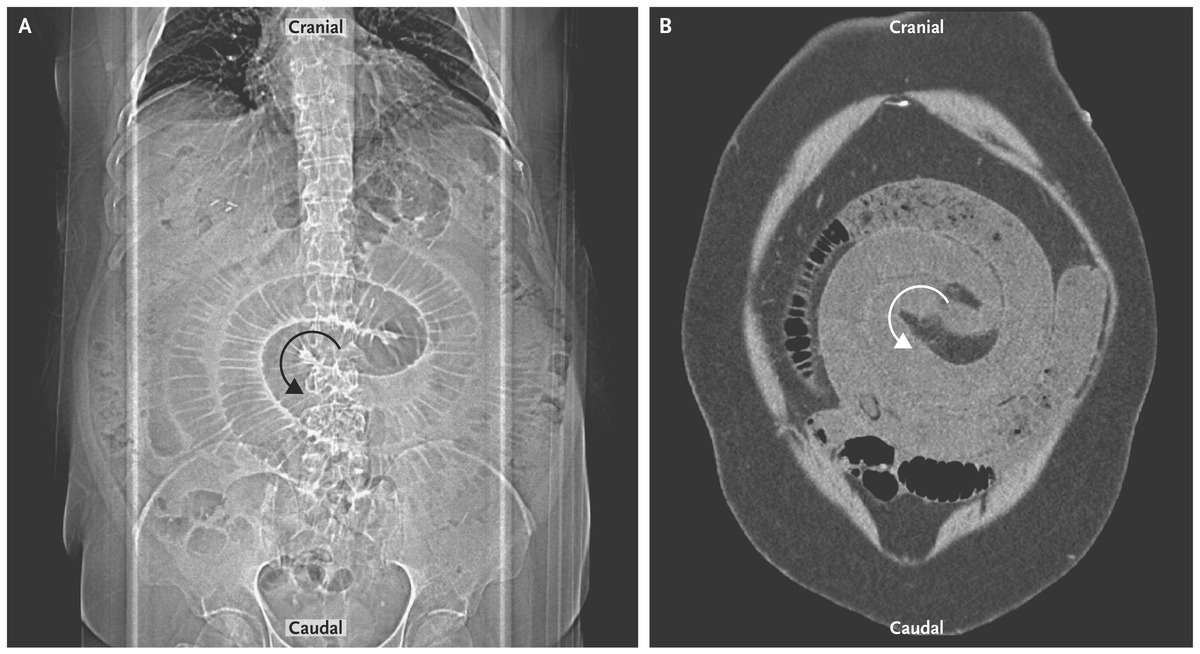

Radiography (Panel A) and computed tomography (CT) (Panel B) showed dilated loops of small bowel distal to the jejunojejunostomy staple line with proximal decompression. Swirling of the bowel and mesenteric vessels was noted on CT as they herniated through the jejunojejunostomy mesenteric defect.

Exploratory laparoscopy showed an internal hernia of the small bowel. The herniation was reduced and the defect closed.